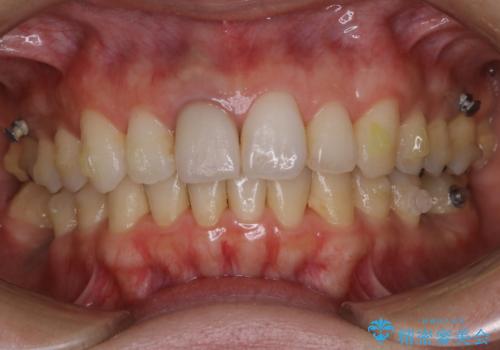

- インビザラインでのマウスピース矯正中にステインや着色を取りたいとのことでした。

PMTC60分コースを行いました。

PMTC(保険外治療)は、毎日の歯磨きで落としきれない汚れや、コーヒ、紅茶・タバコのヤニなどの着色も除去します。目には見えない歯と歯の間・歯肉の境目・インビザライン中はアタッチメント周囲などに残っているプラーク(歯垢)もしっかり取り除きます。PMTCでは専門的な機械や材料を使用して、徹底的に汚れを除去するため、虫歯・歯周病・口臭予防などにつながります。

またPMTCを行うことで、ご自身本来の歯の色になり自然な明るさになります。